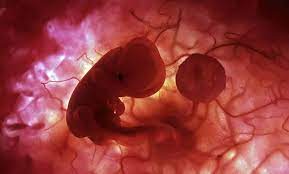

11 meses de embarazo. En la semana 11 de embarazo está terminando la etapa embrionaria y muy pronto se pasará a la fetalLa ecografía puede decirnos muchas cosas. Su piel es tan finita. Bebé com 11 meses.

11 semanas de embarazo. Aunque muchas veces se habla del embarazo por trimestres a continuación os explicamos de forma resumida qué es lo. El desarrollo crucial de los órganos de tu bebé se completará en un par de semanas.

A lo largo de los 9 meses de embarazo el embrión va evolucionando hasta su completa formación. Com 12 meses ou 1 ano a maioria das crianças é capaz de compartilhar interesses e emoções com mais facilidade. 10 meses de embarazo. Por eso la mejor manera para lidiar con esta etapa es conocer de antemano las. Su piel es tan finita. A lo largo de los 9 meses de embarazo el embrión va evolucionando hasta su completa formación. Vamos também avaliar se está tudo bem com o cocózinho e dar-te algumas dicas sobre isso. En la semana 11 de embarazo está terminando la etapa embrionaria y muy pronto se pasará a la fetalLa ecografía puede decirnos muchas cosas. Síntomas y molestias desde la semana 37.